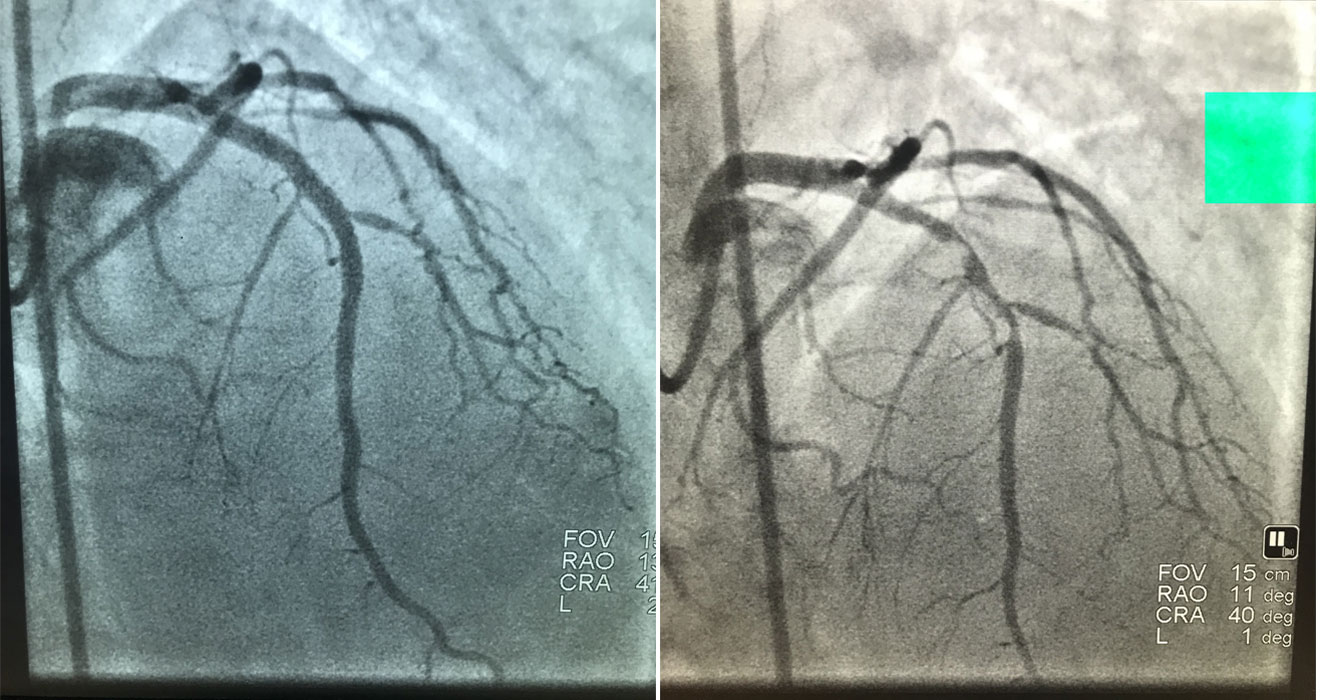

Coronary Angiogram

- State-of-the-Art Technology: We use the latest in medical imaging and interventional tools to ensure accurate diagnosis and effective treatments.